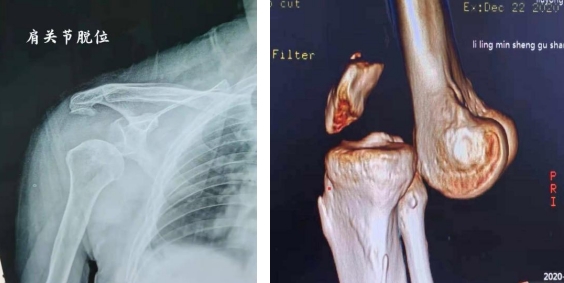

【收治病种】主要收治肩关节、肘关节、腕关节、髓关节、膝关节、踝关节等运动损伤和关节不稳(包括半月板损伤、交叉韧带损伤、肌腿损伤、骨骼肌及关节侧副韧带损伤、股关节损伤与不稳、骨与骨软骨损伤、滑膜病变、肩袖损伤、肩关节不稳、关节孟唇损伤、肩峰撞击综合征、踝关节反复扭伤、韧带肌睫等附着部位撕脱骨折、髓踝关节撞击等)患者。

各种关节脱位伴随韧带损伤,或保守治疗后出现习惯性脱位,也可行手术干预治。